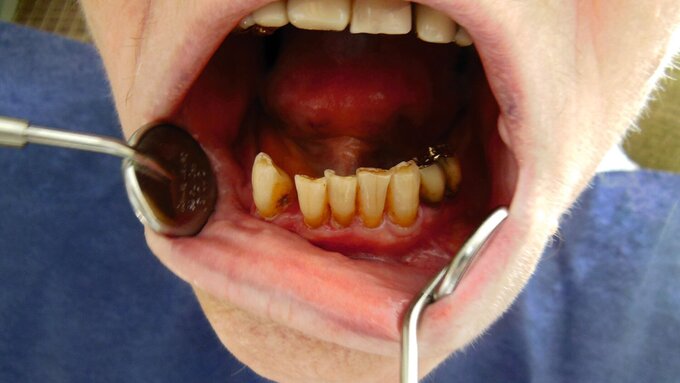

Zudem werden viele ältere Menschen wahrscheinlich mehr eigene Zähne besitzen und möglicherweise höhere Ansprüche bezüglich ihrer Mundgesundheit haben. Damit werden auch die Anforderungen an die Prävention und die therapeutischen Maßnahmen steigen. Auf den ersten Blick scheint es so, dass die zahnärztlichen Maßnahmen bei alten Menschen nicht signifikant von denen bei Jüngeren abweichen – im Detail ergeben sich aber durchaus Unterschiede bezüglich der Behandlungsmöglichkeiten und -maßnahmen: Mit zunehmendem Alter nimmt die Häufigkeit von Krankheiten zu, die zu Mundgesundheitsproblemen führen können. Es ändert sich die Sichtweise bezüglich der Inanspruchnahme zahnmedizinischer Leistungen und die subjektive Wahrnehmung korreliert häufig nicht mehr mit dem objektiven Befund. Außerdem gibt es immer mehr Menschen mit erheblichem Pflegebedarf. In dieser Patientengruppe ist der Karies-Sanierungsgrad wesentlich geringer als bei älteren Seniorinnen und Senioren, die keinen Pflegebedarf haben. Bei der Umsetzung von individuellen Präventionskonzepten ist neben der Etablierung einer altersgerechten Mundhygiene, der Anwendung von Fluoridpräparaten und dem Einsatz unterschiedlicher Biofilm-modifizierender Präparate einer Veränderung der Ernährungsgewohnheiten Aufmerksamkeit zu schenken.

Für die Praxis bedeuten diese Fakten, dass bei Seniorinnen und Senioren ein verstärktes Augenmerk auf Präventivmaßnahmen unter Berücksichtigung der Zunahme freiliegenden Wurzeldentins gerichtet werden muss. Zudem werden vermehrt Austauschrestaurationen erforderlich werden. Da bedingt durch den Abbau des parodontalen Stützgewebes Wurzelkaries-Läsionen zunehmen werden, müssen neue Restaurationskonzepte Eingang in die Praxis finden. Dabei sollte im hohen Alter und bei Patienten mit schlechtem Allgemeinzustand die Erneuerung von Restaurationen mit Augenmaß vorgenommen werden. Vermutlich wird also die Anzahl von Reparaturmaßnahmen zunehmen.